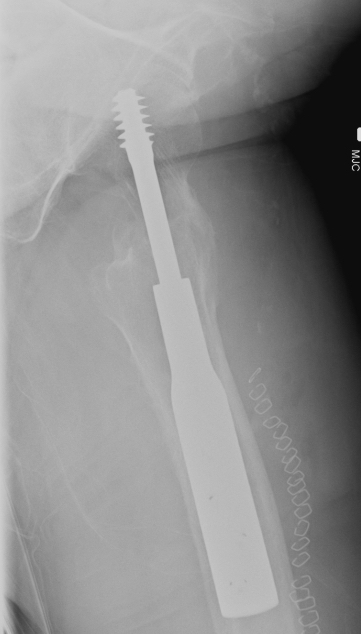

Screw Cut

Causes

- malreduction

- poor screw position / high tip apex distance

- poor bone quality

- Retrospective review of 198 intertrochs treated DHS

- none < 25mm cutout. > 25mm strong predictor of cut-out

Options

- revised to 95o DCS

- hemiarthroplasty / THA